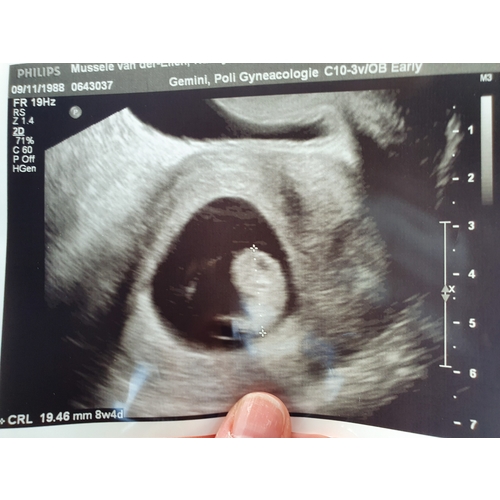

Hier een grove fout van de verloskundige.. Gynaecoloog zag een prachtig bab ...

Dank jullie wel. We zijn heel blij. Was een rollercoaster van emoties. 27 m ...